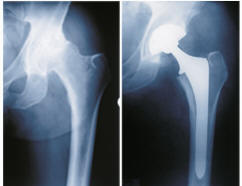

This may be a useful drug for routine use after hip implants to maintain bone health – after all, the femur gets it head cut off, or resurfaced, and/or reamed out and a lump of metal jammed in it!!!

Aledronate Tied to Less BMD Loss Around Femoral Implants

Bone mineral density is maintained in all regions around femoral implants in patients undergoing hip arthroplasty who are treated with alendronate, whereas in the lumbar spine, bone mineral density is higher in patients treated with alendronate or alfacalcidol, according to a study published in the July 6 issue of The Journal of Bone & Joint Surgery.S nEchelon

TUESDAY, July 12 (HealthDay News) — Bone mineral density (BMD) is maintained in all regions around femoral implants in patients undergoing hip arthroplasty who are treated with alendronate, whereas in the lumbar spine, BMD is higher in patients treated with alendronate or alfacalcidol, according to a study published in the July 6 issue of The Journal of Bone & Joint Surgery.

Naoyuki Iwamoto, M.D., from the Yokohama City University School of Medicine in Japan, and colleagues compared the effects of alendronate and alfacalcidol on BMD around the femoral implant and in the lumbar spine after total hip arthroplasty in 60 patients with osteoarthritis of the hip. Patients were treated with alendronate, alfacalcidol, or no medication. Biochemical markers were measured before surgery, and periprosthetic and lumbar spine BMD was measured one week after surgery and again at 12, 24, and 48 weeks. The periprosthetic measurement area in the femur was defined as Regions 1 to 7, sequentially positioned around the implant.

The investigators found that the alendronate group maintained BMD in all regions; whereas, in the alfacalcidol and no-medication groups, BMD in Region 7 was lower than in Regions 3 to 6. At 48 weeks, the alendronate and alfacalcidol groups had higher BMD in the lumbar spine than the no-medication group. The alendronate group had significantly lower serum N-terminal telopeptides of type-1 collagen levels than the no-medication group.

“Alendronate prevented bone mineral density loss around femoral implants, particularly in Region 7 (calcar), but alfacalcidol did not show any effects in any regions. However, bone mineral density losses in the lumbar spine were effectively prevented by either alendronate or alfacalcidol,” the authors write.